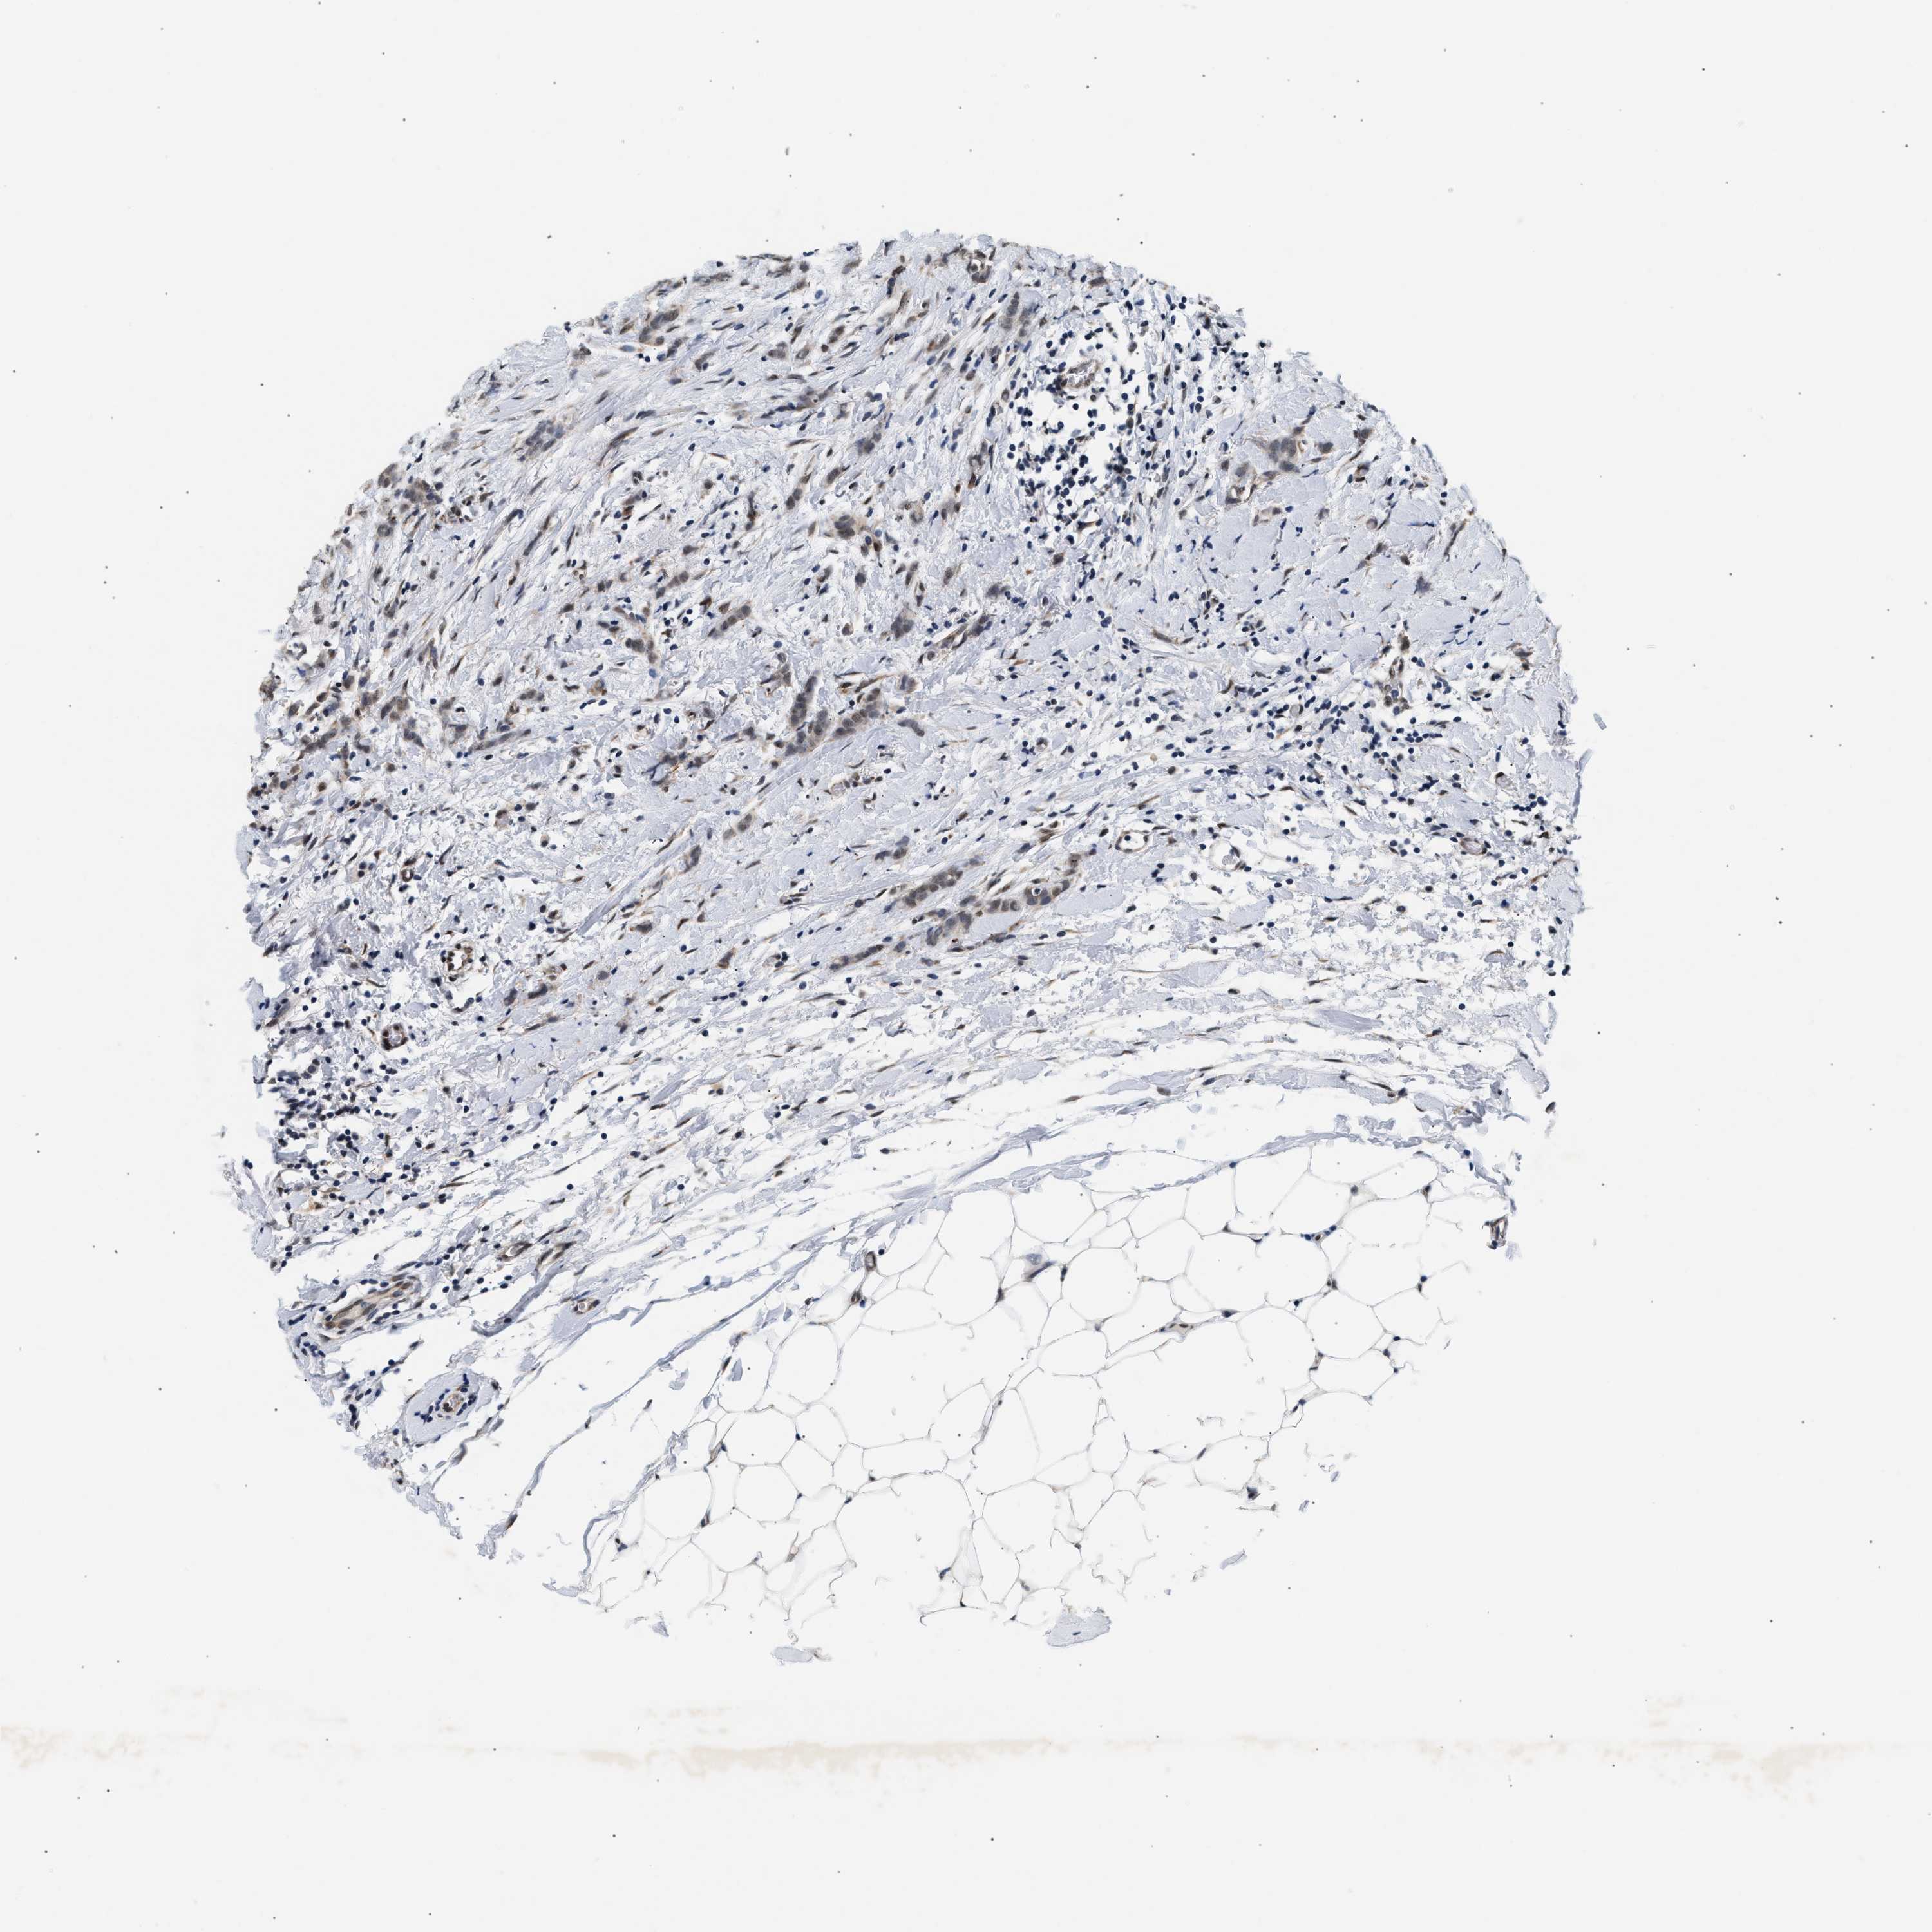

CANCER BREAST CANCER Show tissue menu

BRCA TCGA BRCA VALIDATION PROTEIN EXPRESSION